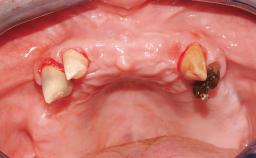

Immediate Loading of Eight Implants in the Maxilla and Six Implants in the Mandible and Final Restoration with Three-Unit and Four-Unit FDPs

Extensive scientific evidence has confirmed that immediately loaded implants with fixed full-arch provisional restorations can osseointegrate with success rates similar to conventionally or delayed loaded implants. A number of immediate-provisionalization techniques for edentulous jaws have been described. Some protocols differ when it comes to prefabricated provisional templates versus complete denture conversion; intrasurgical impressions versus direct relining; and cemented versus screw-retained provisional restorations. In this context, complete-denture conversion has been proposed for either intrasurgical impressions or direct relining. Another possibility is the utilization of a prefabricated provisional to be adapted either in the mouth (by direct relining) or in the laboratory (on a working model obtained from an intrasurgical impression).

Case Type Edentulous Maxilla

Jaw Maxilla and Mandible

Area Full-Arch

# of Teeth All

# of Implants 14